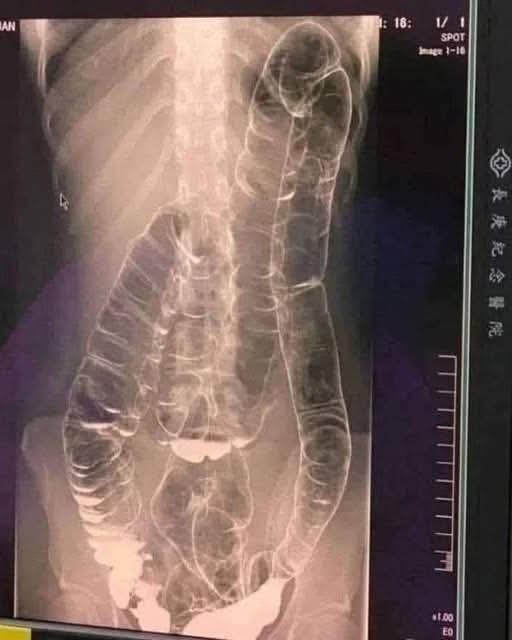

In a shocking medical case that drew attention worldwide, doctors encountered an X-ray of a woman who had suffered from two full weeks of constipation. The image revealed a colon so enlarged from trapped waste that it had expanded upward toward her chest, dangerously close to her heart. The excessive buildup had stretched the colon far beyond its normal limits, causing the organ’s natural folds—essential for healthy bowel movement—to flatten completely. This extreme distension compromised the colon’s ability to push waste forward, putting her at risk of a potentially fatal intestinal rupture.